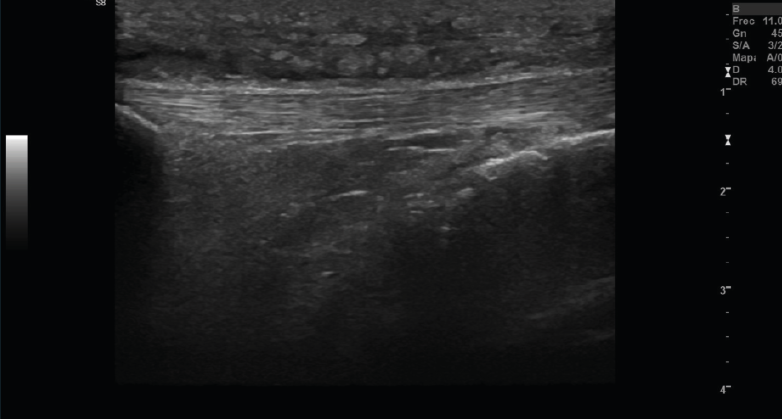

2. Tendones

2.1. Tendinitis

Con ecografía Doppler pueden aparecer áreas de hiperemia intratendinosa o peritendinosa (Figura 8).

Figura 8. Corte sagital de una ecografía de rodilla del tendón rotuliano: engrosamiento del tendón con aumento difuso de ecogenicidad.